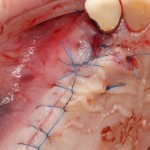

На имплантат ставим формирователь, ушиваем лунку. Напомню, что любой биоматериал должен быть герметично запечатан в ране (фактор успеха III). В противном случае, от него больше вреда, чем пользы:

Совсем уж стягивать края раны не нужно (если бы мы использовали обычный Bio-Oss, то это было бы необходимо). Отличие Bio-Oss Collagen еще и в том, что он не размывается при кровотечении.

Через неделю можно снять швы. Область раны выглядит следующим образом: